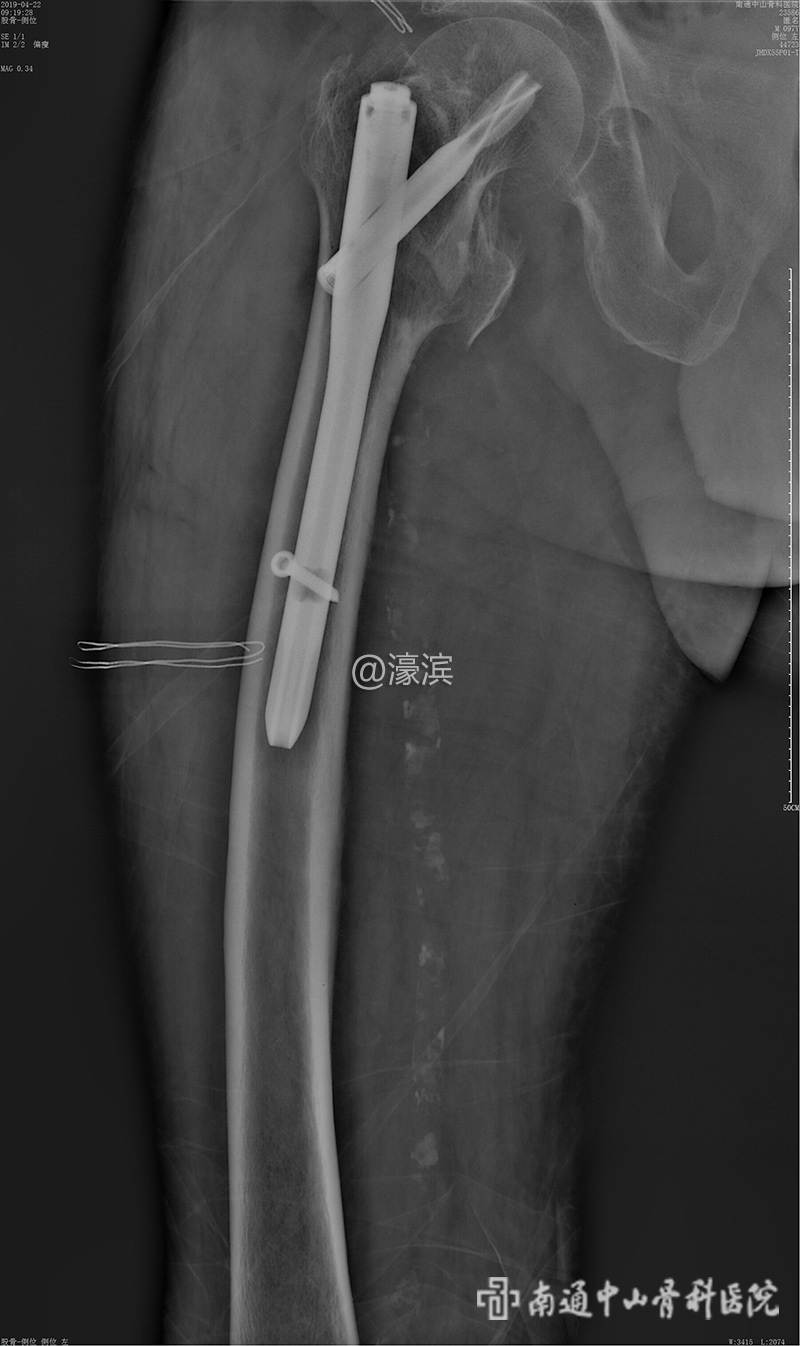

【案例】97岁高龄老人在我院成功接受“右侧股骨粗隆间骨折闭合复位内固定术”

近日,我院在创伤骨科郭建陈主任的带领下,成功为97岁高龄老人实施了“右侧股骨粗隆间骨折闭合复位内固定术”。" Z& _) p: G0 z1 N8 r6 R! k

; }* S# M; e$ B% \  f$ r+ e  4月20日11:30分,周老先生被推入手术室,在麻醉科、手术室医护人员的协作下,12:40分手术成功完成,郭主任团队再次挑战高龄。术后,在全科医护人员及家属的精心照料下,周老先生正在逐渐康复中。- z9 E1 Y- f" F+ @: g; }" L0 k

▲术后